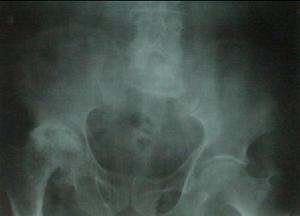

X線應照雙髖內鏇150~200前後位,及屈髖外展各900蛙式(Lauenstein)位及側位片,可從兩個角度上觀察壞死區大小及位置。症狀之初X線片無改變,6~8個月後開始出現骨質稀疏及密度不均,以後軟骨下區出現囊樣變及新月征,股骨頭負重區軟骨下骨質密度增高,其周圍可見點片狀低密度區;病變進一步加重,負重區軟骨下出現碎裂、塌陷,後期全部或部分區域出現不均勻的硬化、嚴重塌陷,股骨頭不規則扁平,關節間隙狹窄,呈半脫位,Shenton線不連續。

4.X線表現:早期股骨頭輪廓正常,但在側位相上,在股骨頭前側面持重區關節軟骨下的骨質中,可見一條1~2mm寬的密度減低的弧形透明帶,構成“新月征”。這一徵象有重要價值。隨之出現持重區軟骨下骨質密度增高,其周圍可見點狀、片狀密度減低區及囊性改變。最後軟骨下骨質呈不同程度碎裂、扁平、塌陷,股骨頭變扁平、塌陷、半脫位狀。可見骨性關節炎改變。

II期:臨床症狀繼續加重,X線片表現為骨密度增高及囊樣變,軟骨下骨出現弧形透光帶,稱新月狀征(Crescent sign),但股骨頭外形仍正常。

III期:病髖疼痛妨礙行動,各方活動已明顯受限,X線片股骨頭邊緣因塌陷而有重疊,或已失去圓形,硬化區明顯。診斷雖易定,處理卻已困難。

IV期:病程已至晚期,股骨頭變形,關節間隙狹窄,髖臼硬化,出現明顯的骨關節炎病徵。